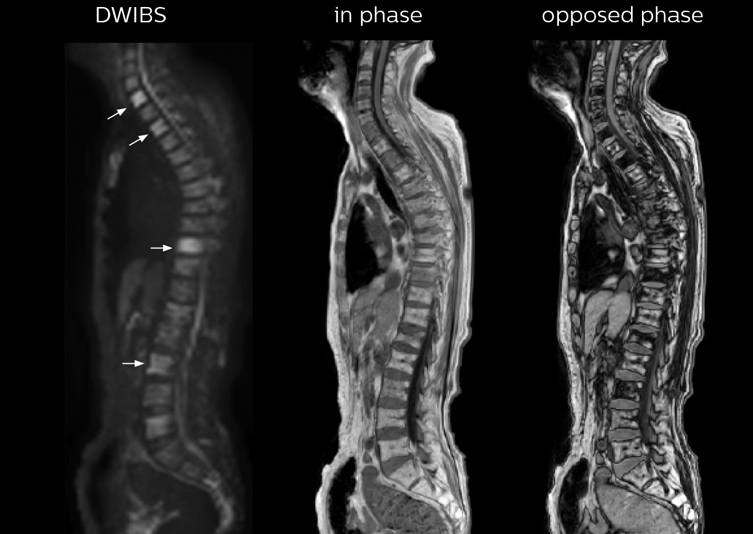

“In-phase and out-phase sagittal T1-weighted FFE images help us to visualize and further characterize bone lesions such as metastasis and bone-marrow hyperplasia that have high signal on DWI. These images are also used throughout radiotherapy, to monitor changes in the fatty bone marrow.”

“mDIXON FFE allows us to quickly get information we need to assess the presence of fat. That gives us more information when we need to diagnose bone lesions, and when we are asked to judge fat-containing lesions such as hepatocellular or renal carcinoma,” Dr. Nobusawa says. “The mDIXON fat images can help us to differentiate fatty bone marrow from bone lesions. This is especially useful in elderly people, who tend to have fattier bone marrow. The water images provide a high signal-to-noise ratio in the intestinal canal, which is valuable for visualizing lesions in the colon,” he says.

Kawasaki Sawai Hospital’s whole body protocol also includes an mDIXON FFE sequence. Because mDIXON provides images for four contrast types – water only, fat only, in-phase and out-of-phase – from a single acquisition, it is useful in many ways.